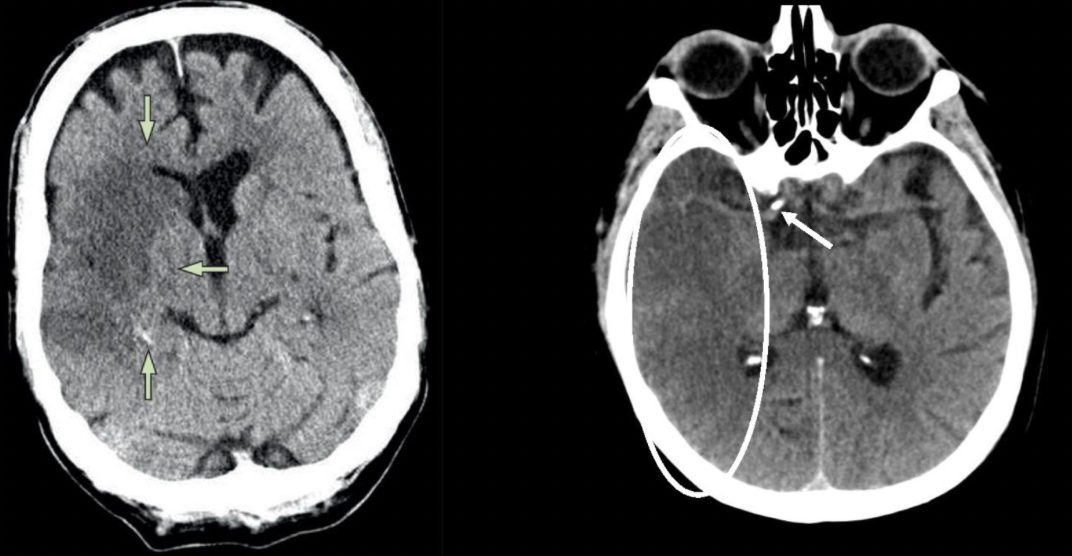

20

Diagnóstico

A

EVC isquémicoen fase crónica

19

Características del EVC isquémico en fase crónica

De meses a años

Encefalomalacia

Hipodensidad a nivel de líquido

Efecto de masa negativo-retracción de ventrículos

31

En dónde tiene su hallazgo la causa hipertensiva en EVC hemorrágico

Ganglios basales 80% Cerebelo Tallo cerebral

33

Dx

EVC hemorrágico en ganglios basaeles